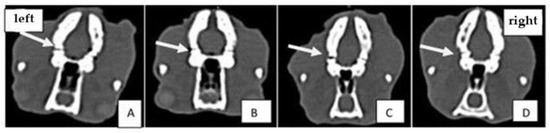

2.3. Computed Tomography (CT) Analysis

4.4. Computed Tomography (CT) Analysis